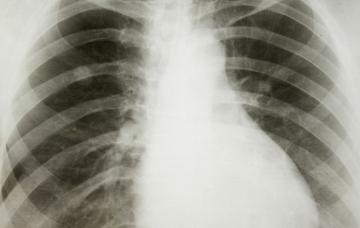

Diagnóstico del cáncer de pulmón

Un diagnóstico temprano del cáncer de pulmón puede evitar que se haya extendido y resulte incurable. Conoce las pruebas que permiten detectarlo.